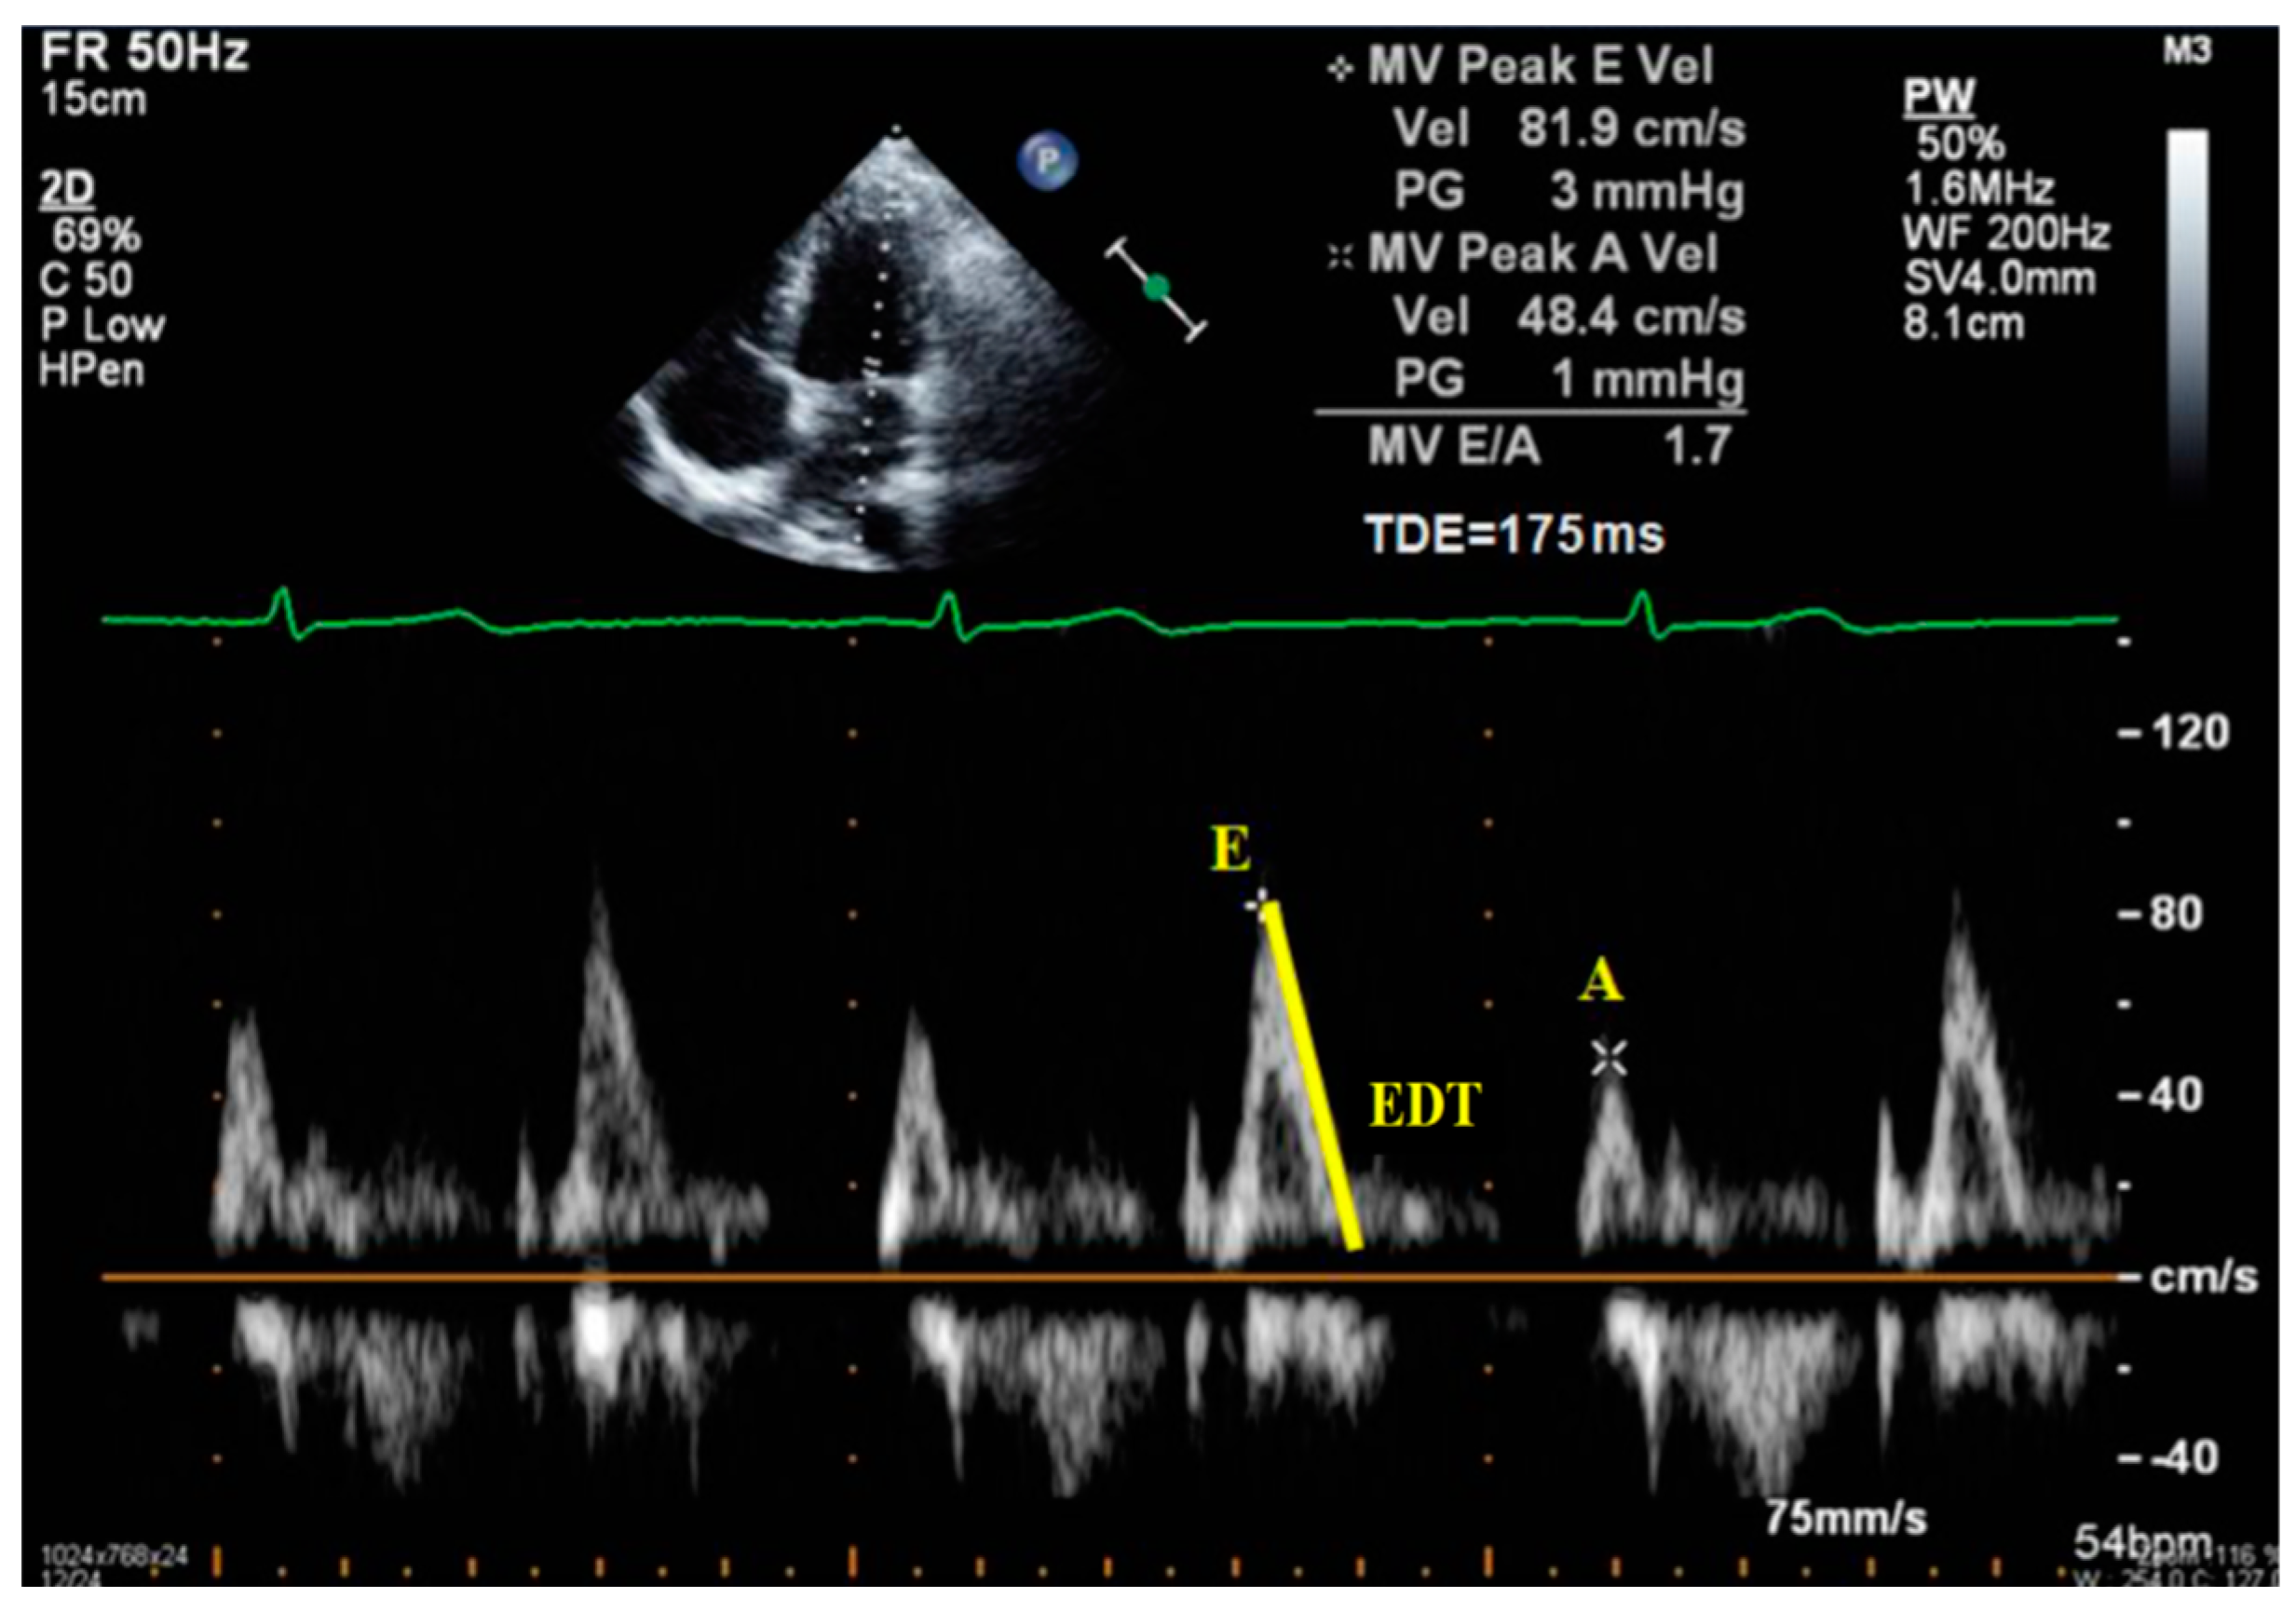

- Peak of passive filling (E wave), peak of active filling (A wave), E/A ratio, deceleration time of E wave (EDT) with pulsed Doppler (Figure 3);